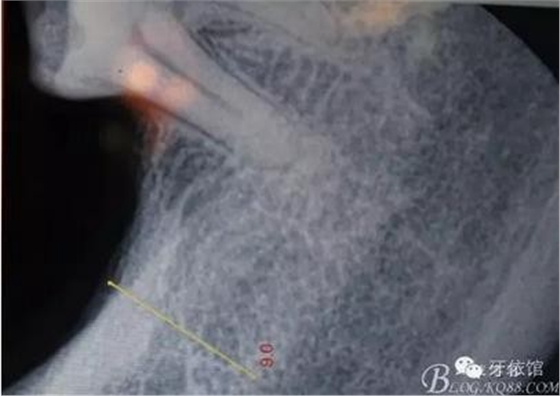

先在右上7的位置擴孔同時做內(nèi)提升

再在右上6牙根間隔擴孔、內(nèi)提

間隔上備的洞內(nèi)可以看到上頜竇膜